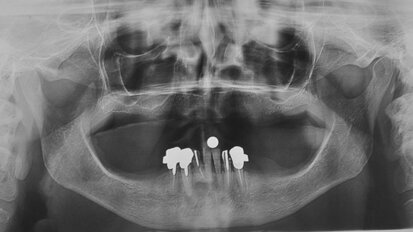

Impianti short a carico immediato in grave atrofia mandibolare

La chirurgia ricostruttiva preimplantare non può essere praticata in tutti i pazienti a causa di possibili controindicazioni locali e/o sistemiche. ...